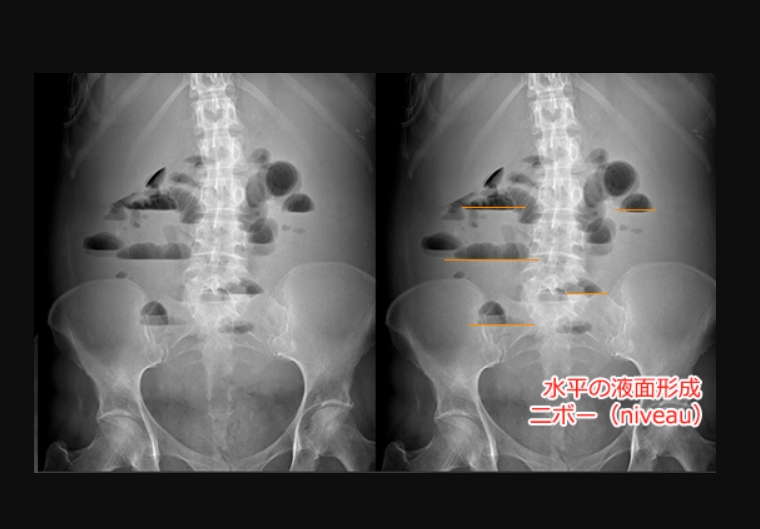

出典:イレウス(腸閉塞)を理解して、腹部X線写真(レントゲン)のポイントを押さえる! | RadioGraphica

・イレウスが疑われるとき、まず初めに行うべき検査で立位と臥位の像の比較が重要である。

・立位における鏡面形成(二ボー像)と、臥位における小腸ガス像は機械的イレウスに特徴的な所見であるが、上部空腸での閉塞や絞扼性イレウスで小腸ガスの拡張像がないこともあり注意が必要。